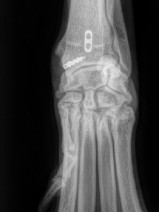

• 19ème Cours de Propédeutique, sémiologie et pathologie de l'appareil locomoteur : Carpe, tarse et au-delà : explorons les extrémités

Le thème de cette 19ᵉ édition du Cours de Propédeutique, Sémiologie et Pathologie de l’Appareil Locomoteur à Bédoin sera d’explorer les extrémités. Nous poursuivons l’objectif qui fait la force de ce rendez-vous depuis ses débuts : offrir une approche à la fois rigoureuse, pratique et actuelle des affections locomotrices. À travers un programme structuré mêlant rappels fondamentaux, analyse sém...

Orthopédie

Traumatologie